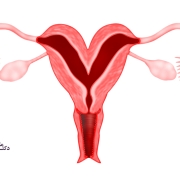

تخمک گذاری چگونه عمل میکند؟

تخمک گذاری، آزاد شدن تخمک (تخمک) از تخمدان و بخشی از چرخه قاعدگی است. به طور متوسط، این در روز 14 سیکل قاعدگی 28 روزه اتفاق میافتد. هورمونهای متعددی در تخمک گذاری نقش دارند.

فرایند تخمک گذاری زمانی شروع میشود که هیپوتالاموس (بخشی از مغز) هورمون آزاد کننده گنادوتروپین (GnRH) ترشح کند. GnRH باعث میشود غده هیپوفیز (غده ای در مغز) هورمون محرک فولیکول (FSH) ترشح کند.

بین روزهای ششم و چهاردهم چرخه قاعدگی، FSH باعث میشود فولیکولها (کیسههای کوچک در تخمدانها که حاوی یک تخمک در حال رشد هستند) در تخمدان شروع به بلوغ کنند. در طی روزهای 10 تا 14 چرخه، تنها یکی از فولیکولهای در حال رشد تخمک کاملا بالغ را تشکیل میدهد. در حدود روز چهاردهم چرخه قاعدگی، افزایش ناگهانی LH باعث میشود که تخمدان، تخمک خود را آزاد کند. به این حالت تخمک گذاری میگویند.

پس از تخمک گذاری، تخمک سفر پنج روزه خود را از طریق لوله فالوپ به سمت رحم آغاز میکند. همانطور که تخمک از طریق لوله فالوپ حرکت میکند، سطح پروژسترون، هورمون دیگری، در بدن افزایش مییابد که به آماده سازی پوشش رحم برای بارداری کمک کند.